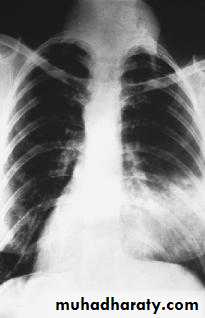

Full investigation

Chest x ray

ECG.

F B S.

B urea.

Blood group

Blood preparation for

transfusion.